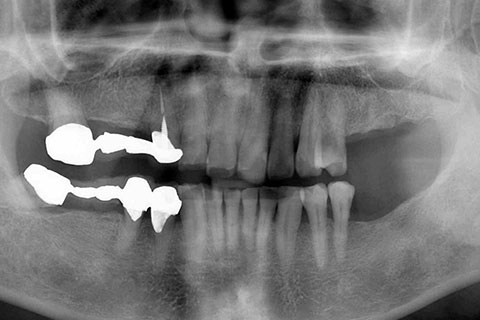

• 症例2

治療前

インプラント埋入時

治療後

年齢・性別

57歳男性

治療期間

3ヶ月

抜歯

なし

治療費

154万円

備考

左上5.6.7 及び左下6.7欠損

治療内容

左上5.6.7と左下6.7欠損部にインプラント埋入

施術の副作用(リスク)

オペによる知覚障害。インプラントによる歯肉炎。インプラント脱落。